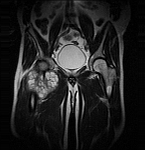

• Tumor surgery of the musculoskeletal system

• Resection of benign and malignant tumors of the bone and soft tissue

• Extensive reconstructive procedures for the reconstruction of large pelvic bone defects